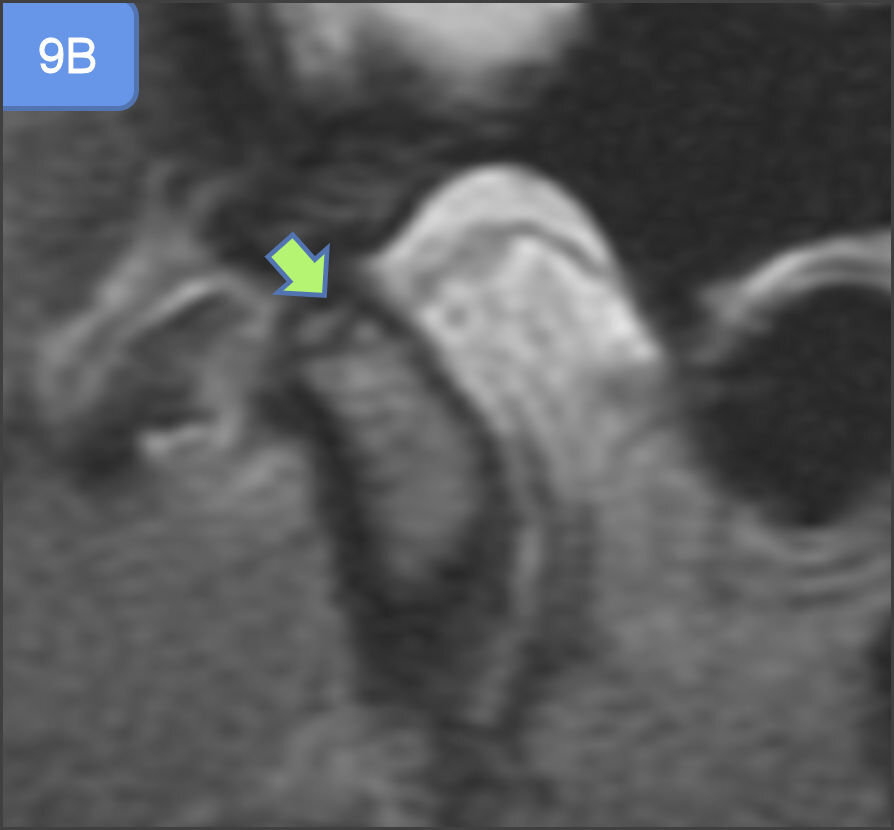

A study done by K Ikeda et al30 which showed that, in case of partial disc displacement(PDD), the condyles were displaced posteriorly in the fossae with a mean anterior space of 2.7 ± 0.5 mm (normal 1.3 ± 0.2 mm) and a posterior space of 1.8 ± 0.4 mm (normal 2.1 ± 0.3 mm). In total disc displacement without reduction (TDDWR), the condyles were displaced not only posteriorly as observed in PDD, but also vertically with a reduced superior space of 1.9 ± 0.4 mm (normal 2.5 ± 0.5 mm). Also, the mean posterior space in case of total disc displacement was further reduced. In the present study, partial displacement (identified by position of posterior band) of disc was more in group III followed by group II, while complete displacement was seen more in Group II (See Figures 6, 7A and 7B) and so was the disc non-reducibility and deformity in open and closed mouth. The inconsistencies in the result might be due to unequal number of joints in each group.

A study done by Emshoff et al,38 revealed, significant relationship between the presence of TMJ bone marrow edema and the MR diagnoses of TMJ internal derangement particularly, disc displacement without reduction and effusion. Although, TMJ internal derangement alone was not always associated with bone marrow edema, it can be present without the evidence of bone marrow edema as well. The association between TMJ bone marrow edema and effusion may be supported by the fact, that the bone marrow abnormalities represent a response to an increased intra-articular pressure in conditions such as synovitis and effusion.39,40 In the present study, Group II followed by Group III (See Figure 8, Figures 9A & 9B) demonstrated highest frequency of bone marrow edema, non-reducibility of disc in open mouth and effusion and hence, was consistent with the findings of previous studies.